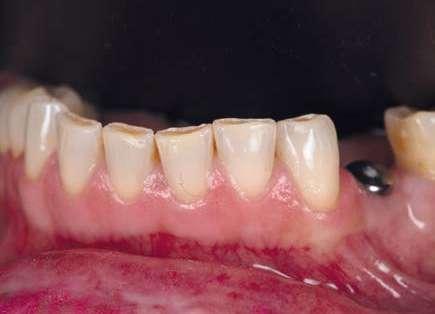

Además, lo combinaremos con unas carillas inyectadas inferiores también planificadas digitalmente y sin tallado, para crear una armonía y equilibrio con la parte superior.

Para la arcada inferior se optó por unas carillas inyectadas, completamente respetuosas con los tejidos, que nos permiten mejorar la apariencia de los dientes y dar así una mayor armonía con la parte superior. Al ser también planificadas digitalmente aseguramos que lo que colocamos en boca sea una fiel reproducción del diseño previamente aceptado por el paciente y el profesional.